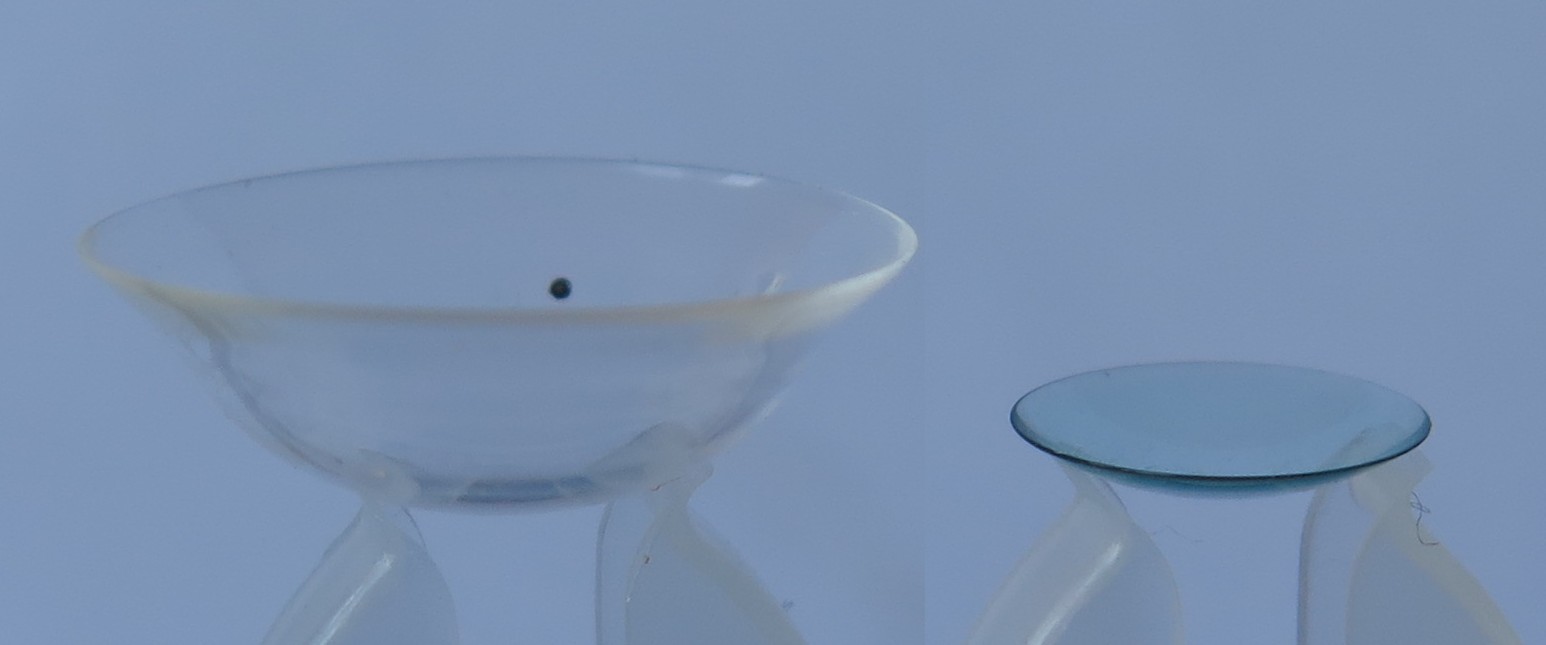

Een kleine greep uit ons aanbod